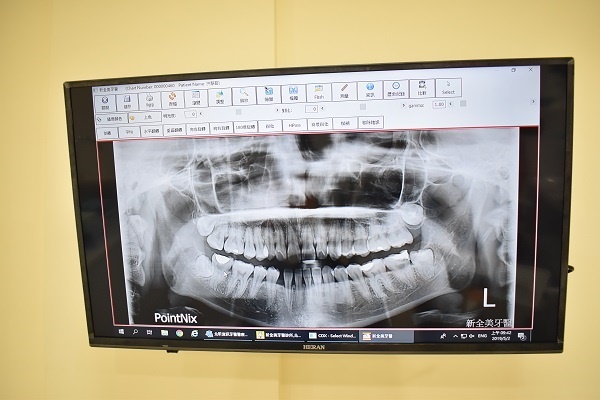

照過X光片才知道媽媽雖然幫我生了一口好牙

雖沒太多蛀牙…不過卻有四顆愛搗蛋的智齒

其中一顆智齒竟還很靠近鼻腔神經需要將牙齦切開才能處理

我的小虎牙會特別突出也是因為水平智齒推擠前牙導致